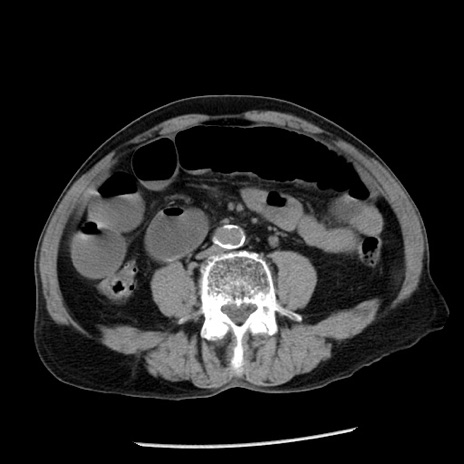

症例26(横断像)

【症例】80歳代男性

【主訴】嘔吐

【現病歴】昨晩2回嘔吐あり、今朝になっても嘔吐あり。来院。

【既往歴】胃潰瘍

【身体所見】意識清明、BT 37.6℃、BP 166/95mmHg、HR 100bpm、SpO2 97%、腹部:平坦・軟、腸蠕動音聴取良好、圧痛なし。

【データ】WBC 21900、CRP 1.46